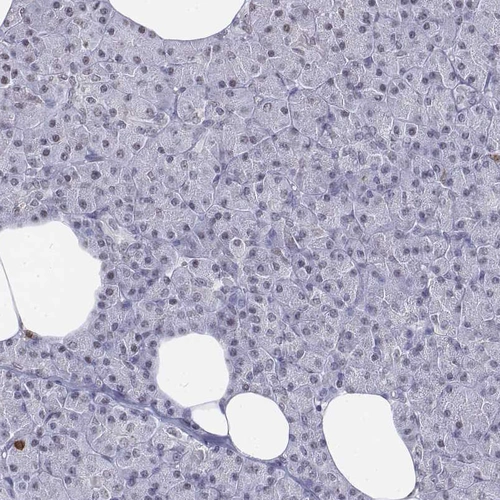

Immunohistochemistry analysis in human lymph node and pancreas tissues using HPA043955 antibody. Corresponding CD3E RNA-seq data are presented for the same tissues.